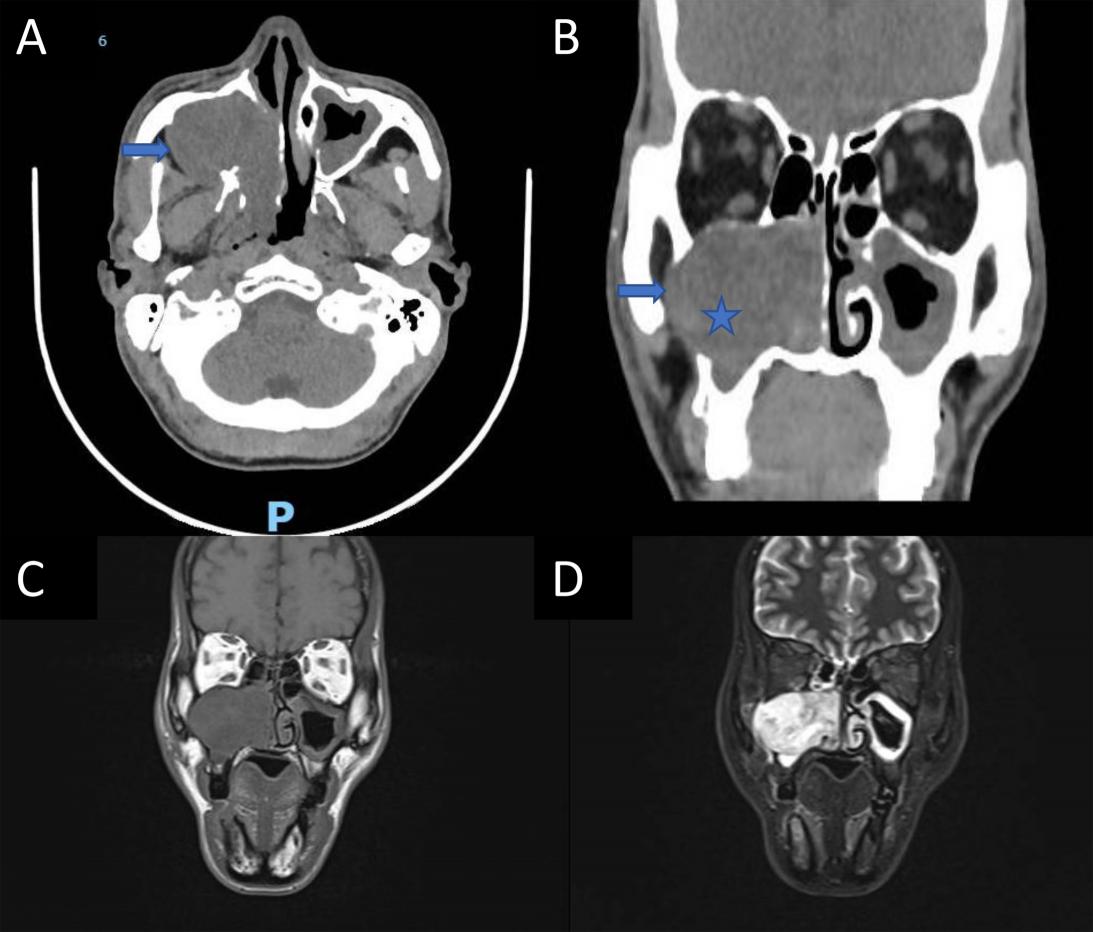

Kết quả xét nghiệm cho thấy tổng số bạch cầu trong giới hạn bình thường (8,85 G/L), tuy nhiên bạch cầu ái toan tăng cao (chiếm tỷ lệ 14,1%, tương đương khoảng 1250 tế bào/mm³). Các chỉ số sinh hóa máu như bilirubin và CRP đều bình thường. Siêu âm ổ bụng ghi nhận tình trạng giãn và dày nhẹ thành đường mật trong gan. Chụp MRI ổ bụng có tiêm thuốc cản quang hướng đến chẩn đoán viêm đường mật với hình ảnh đường mật trong gan giãn, thành dày tăng ngấm thuốc. Các xét nghiệm chuyên sâu tiếp theo xác định bệnh nhân nhiễm sán lá gan bé: xét nghiệm huyết thanh phát hiện kháng thể kháng Clonorchis/Opisthorchis IgG dương tính cao (OD 11,3; giá trị bình thường <1), xét nghiệm phân phát hiện trứng sán lá gan bé. Với biểu hiện lâm sàng và cận lâm sàng trên phù hợp với chẩn đoán: Viêm dày đường mật do sán lá gan bé (Clonorchis sinensis/ Opisthorchis viverrini)